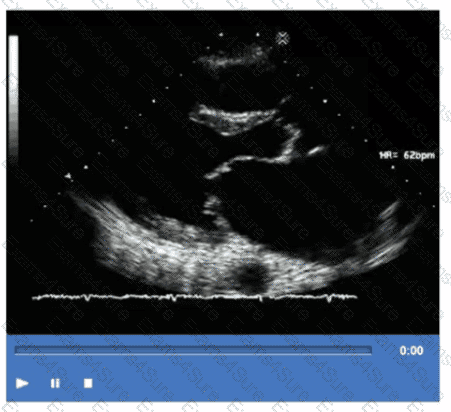

Which of the following is the most likely cause for the findings demonstrated in this video?